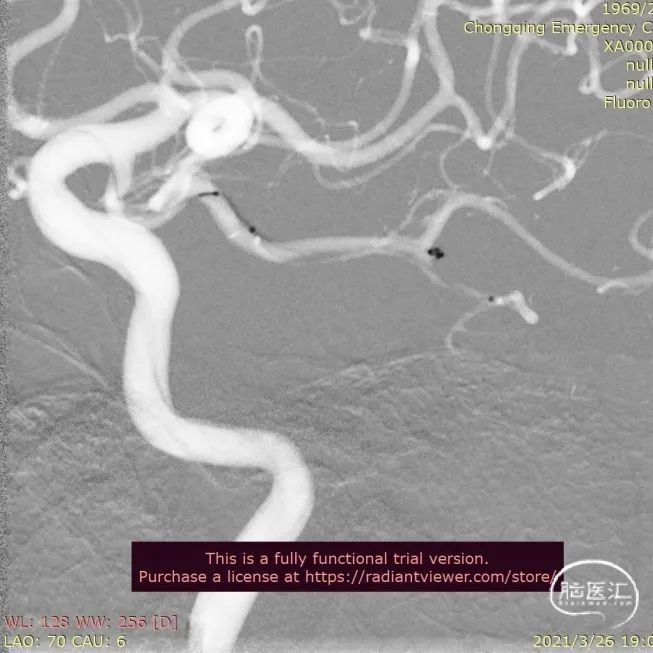

送入3.0mm*15mmNeuroform Atlas支架并释放,头端位于P3段,尾端位于P2段,释放后Atlas支架的Mark点显影良好。观察10分钟,P2段及远端血流仍通畅,未见血栓形成,遂结束手术。

术后即刻影像

治疗后工作位减影造影显示动脉瘤栓塞满意,载瘤动脉血流通畅。

术后CT提示支架打开良好。